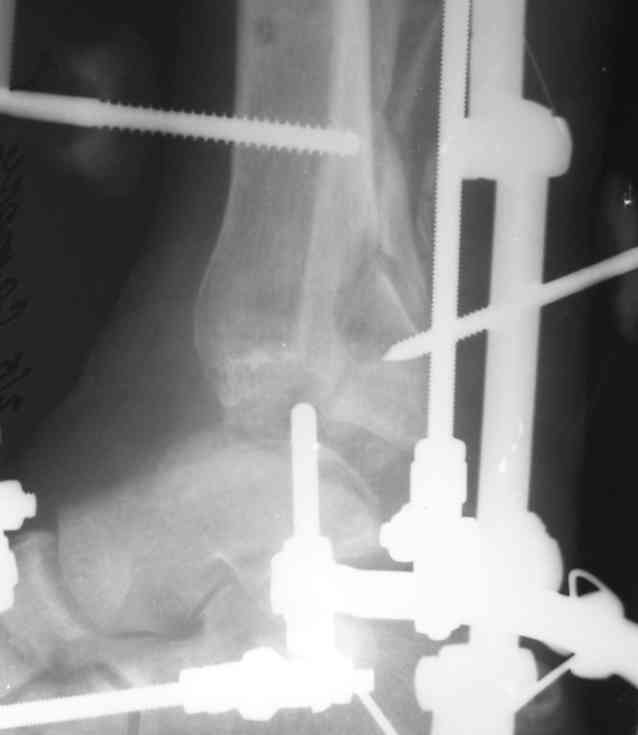

Уважаемый Никита!!! Я думаю в такой ситуации (спасибо за свежие рентгенограммы) будет правильно выполнить :

Радикальную некрэктомию б/берцовой кость с последующим одномоментным закрытием раны перемещённым языкообразным лоскутом. В Последующем- остеотомия в в/з с формированием дистракционного регенерата. Лоскут лучше выкроить с задне-внутр. пов-ти, там кожи больше и она подвижная. Полость надо затомпонировать икроножной мышцей !!!! Ничего страшного нет, всё будет ХОРОШО!!! С уважением Скребцов Владимир

По рентгену мне кажется, что остается ротация проксимального фрагмента.

Залог успеха в лечении осложненных открытых переломов - это создание стабильной конструкции в месте перелома. Сделанная КТ грамма поможет определить вовлечение внутрисуставного компонента, при вовлечении в сустав, для профилактики дальнейшего смещения, мы бы применили пару шурупов в дистальном эпиметафизе, в ваших условиях, стабилизацию аппарата можно достичь дополнительными проведенными спицами и спицами с упорной площадкой на эпифизе.